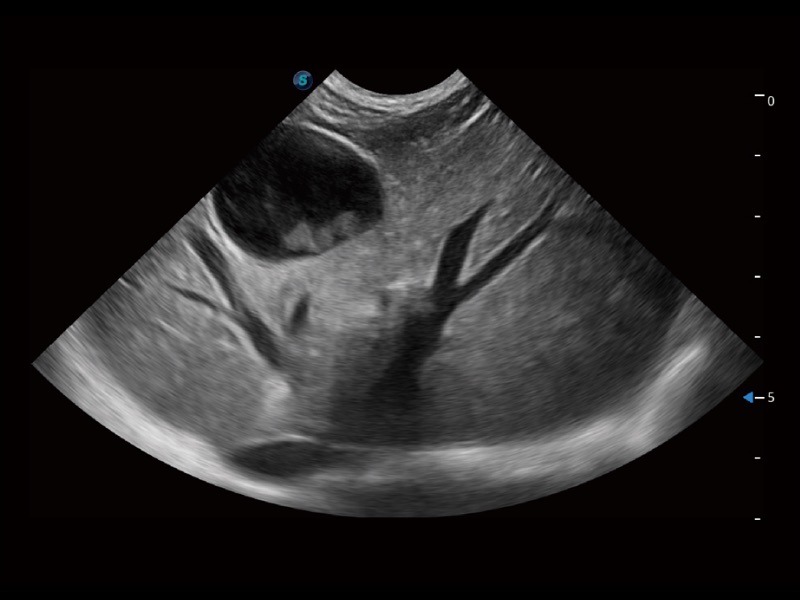

一键自动识别膀胱壁及自动测量膀胱容积,不受膀胱形状和大小的限制,帮助医生快速精准获得测量的数据。

增强穿刺针在动物解剖结构中的位置,提高穿刺介入的安全性和准确性。

操作简便,无需高频度外力作用即可真实反映组织的形变,快速评估肿瘤良恶性。